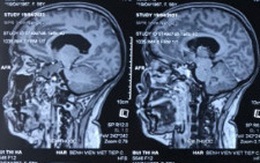

Tưởng bị thiếu máu não, đi khám phát hiện u màng não lớn

Một phụ nữ 56 tuổi (ở Hải Phòng) kể một năm nay thường xuyên đau đầu, bà nghĩ có thể do thiếu máu lên não, nhưng uống thuốc bổ cũng không đỡ.